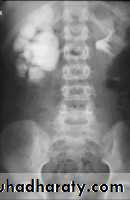

Normal IVU

nephrogram

pyelogram